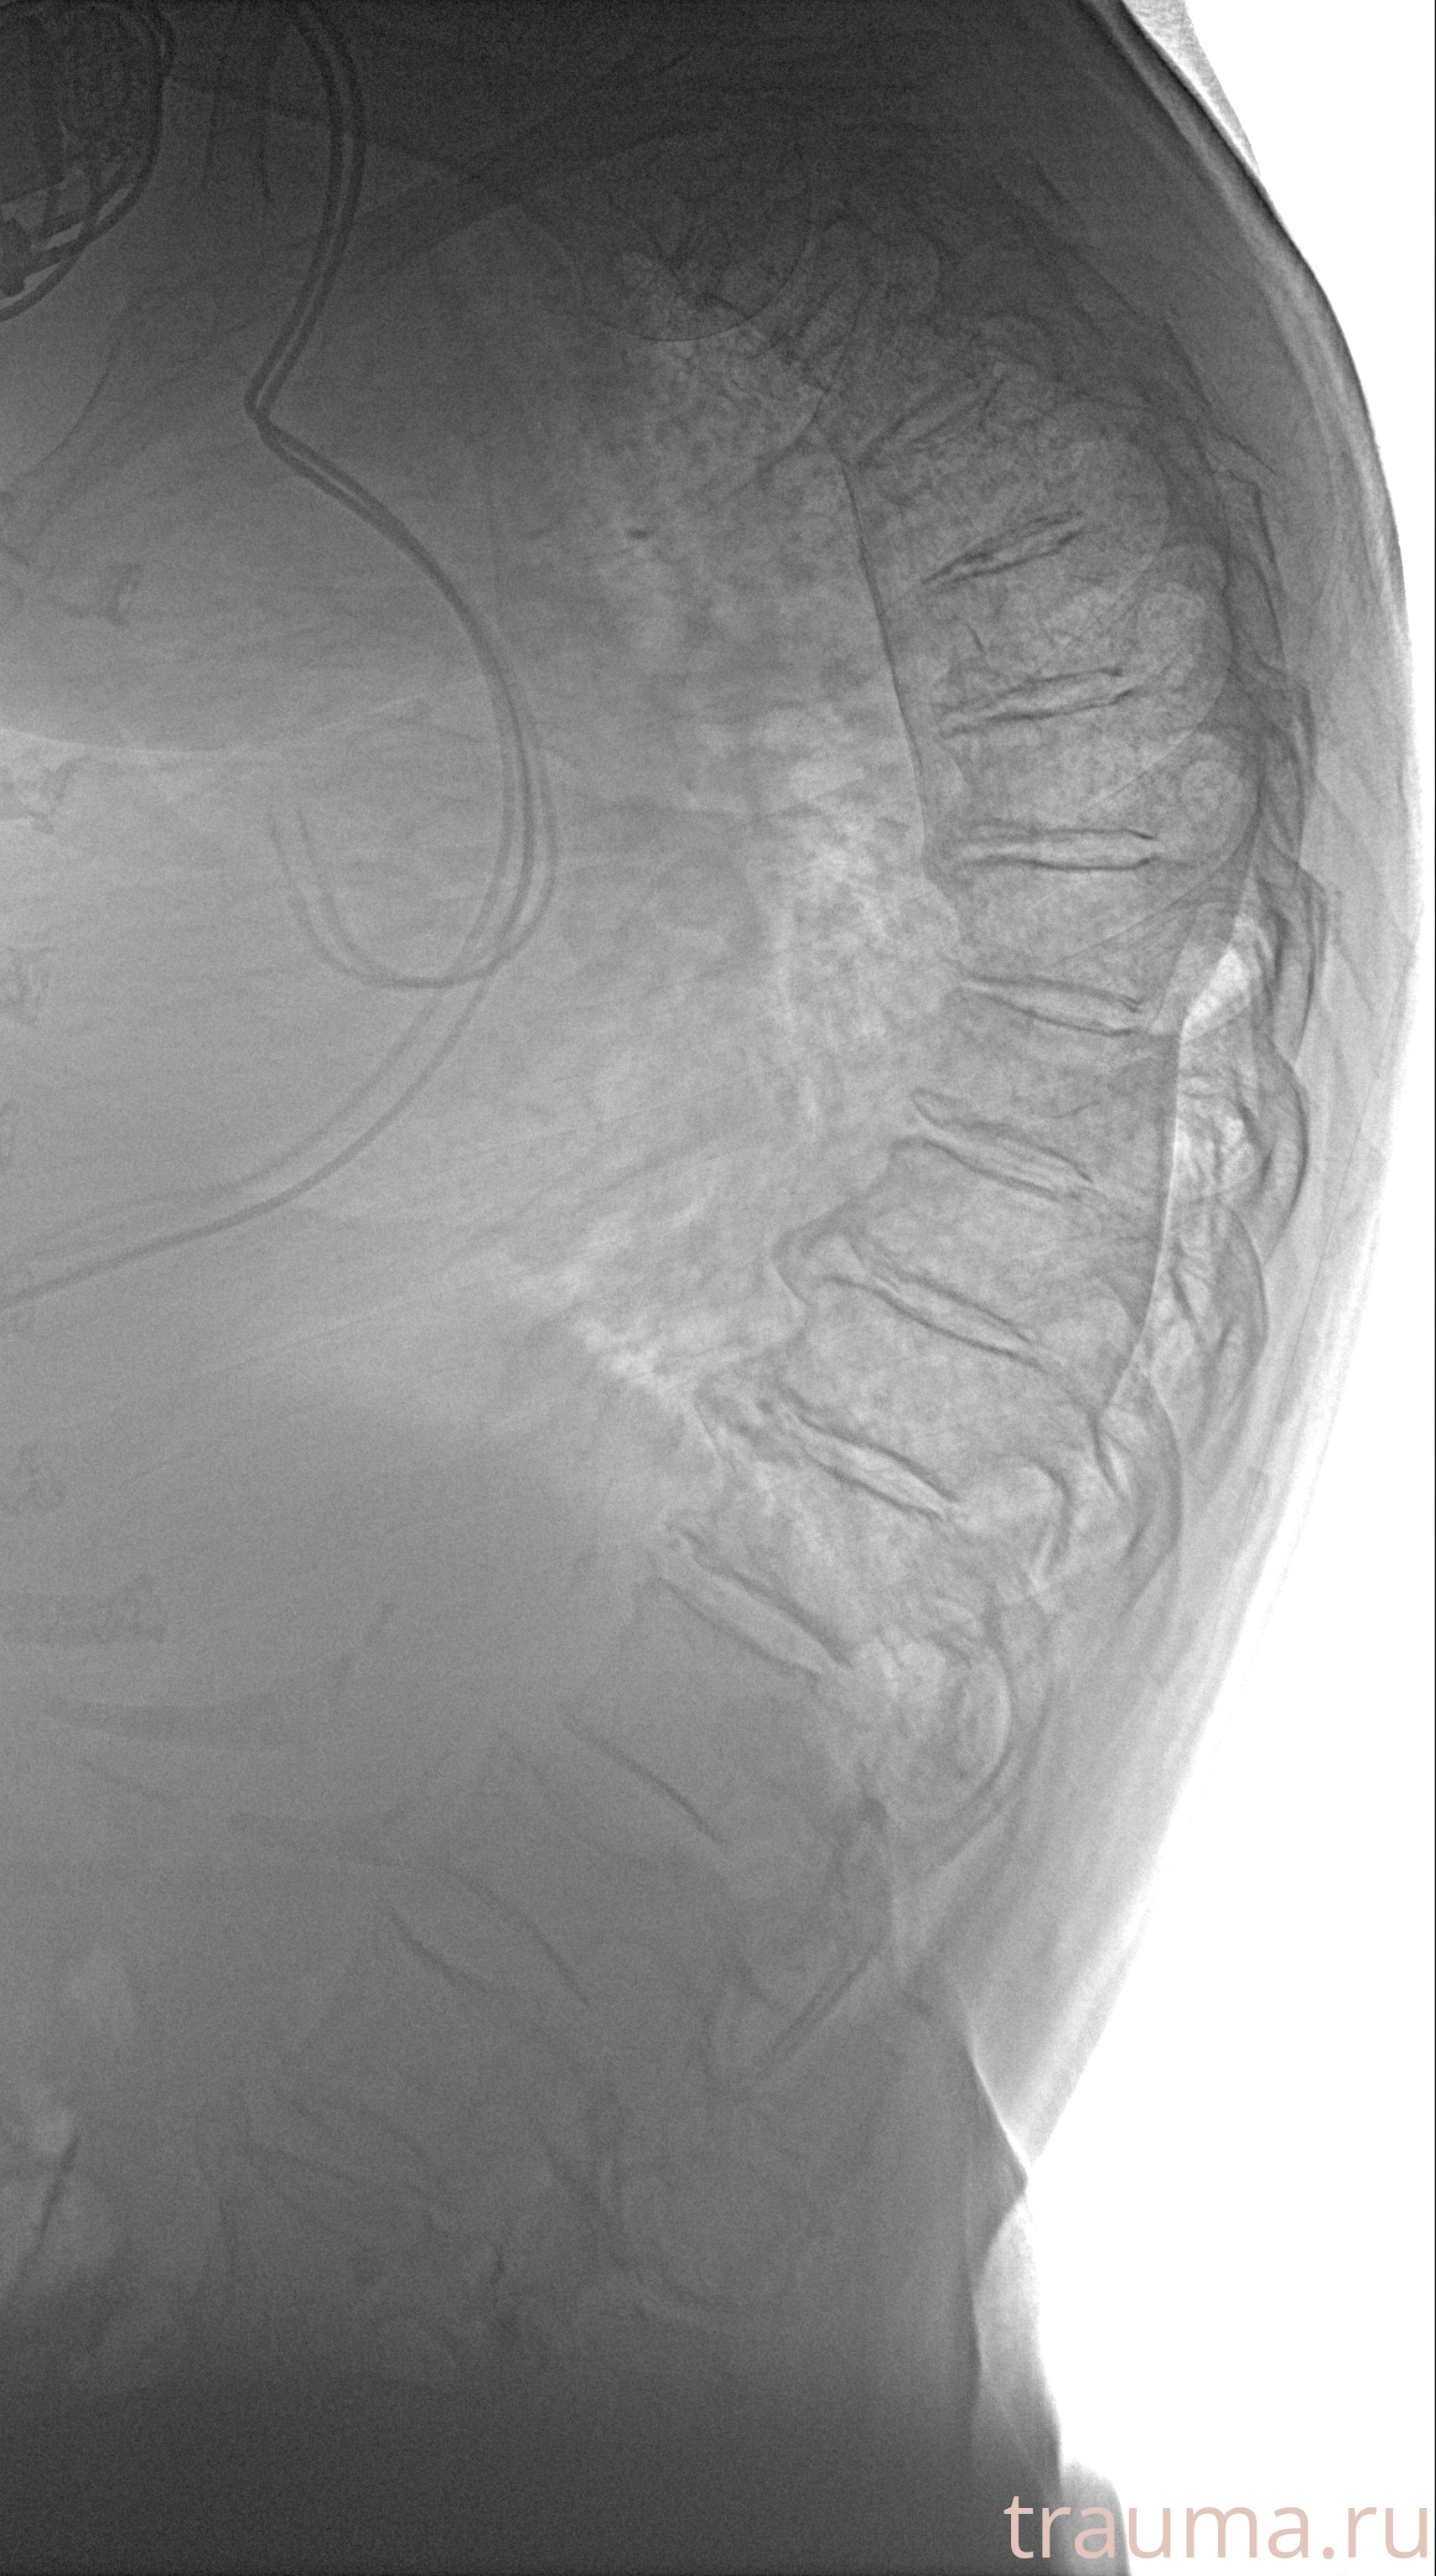

Рентген на дому: по вашему адресу приезжает врач-рентгенолог, травматолог-ортопед с мобильным рентгеновским аппаратом, проводит диагностику травмы или заболевания, делает необходимые рентгенограммы, дает рекомендации по дальнейшему лечению. Получить качественные снимки в домашних условиях возможно благодаря уникальной методике, разработанной МосРентген Центром для института  Склифосовского